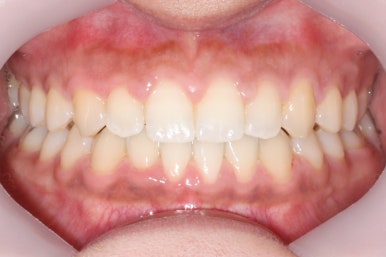

위 사진은 부산치아교정치과에 내원하셨을 대 당시의 입안 모습입니다.

치아들 사이에 전반적으로 틈이 많이 있는 상태입니다.

부산치아교정치과에서 치료한 이 사이가 벌어진 틈새교정을 마무리 했을 때의 모습을 보여드리겠습니다.

몰라보게 바뀌었습니다.

틈새가 다 모였고 다시 틈이 벌어지지 말라고 앞니 안쪽에는 유지장치를 달고 마무리를 했습니다.

전후를 비교해 보겠습니다.

부산치아교정치과 전후 모습입니다.

변화가 놀랍습니다.